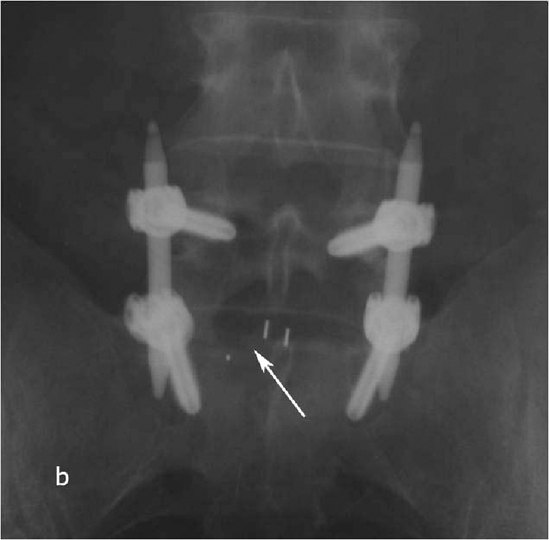

Рис. 2a,b. Рентгенограмма поясничного отдела позвоночника в боковой (а) и прямой (b) проекции после операции транспедикулярной фиксации L4-L5 позвонков. Стрелкой указаны 2 титановых цилиндрических кейджа.

Рис. 6a. Рентгенограмма поясничного отдела позвоночника в боковой (а) и прямой (b) проекции после операции транспедикулярной фиксации L4-L5 позвонков. Стрелкой указаны 2 титановых цилиндрических кейджа. Рис. 6b. Рентгенограмма поясничного отдела позвоночника в боковой (а) и прямой (b) проекции после операции транспедикулярной фиксации L4-L5 позвонков. Стрелкой указаны 2 титановых цилиндрических кейджа.